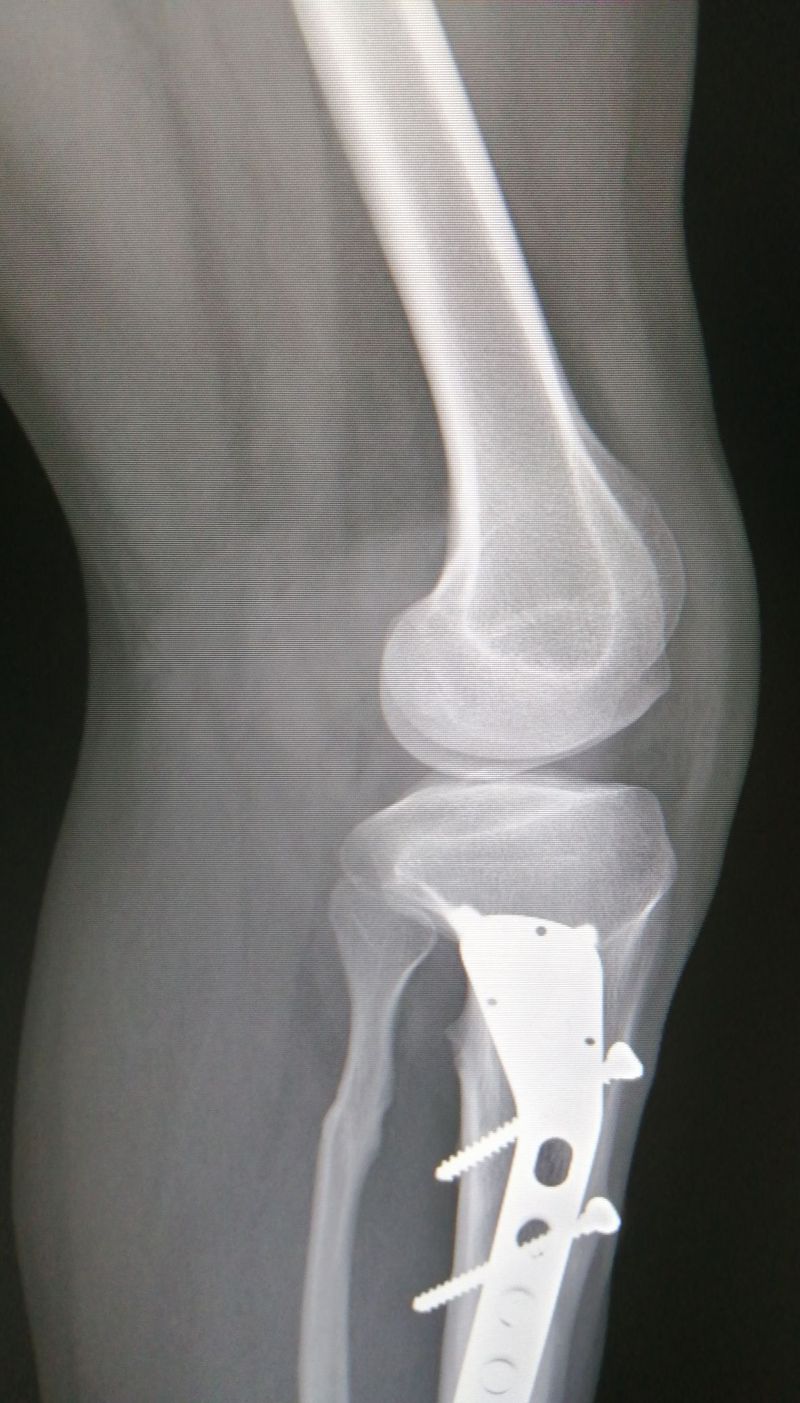

What's wrong with this knee? :)

It is :D But i thought the patella,